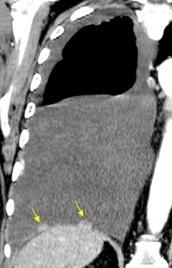

100. TUMOR FANTASMA

En relación con trasudados tabicados. Insuficiencia cardiaca

Derrame pleural “encapsulado”

“Tumor fantasma”

Asociado a fallo cardiaco. ( “Pleuritis adhesiva”). Buch KP. Chest. 2000